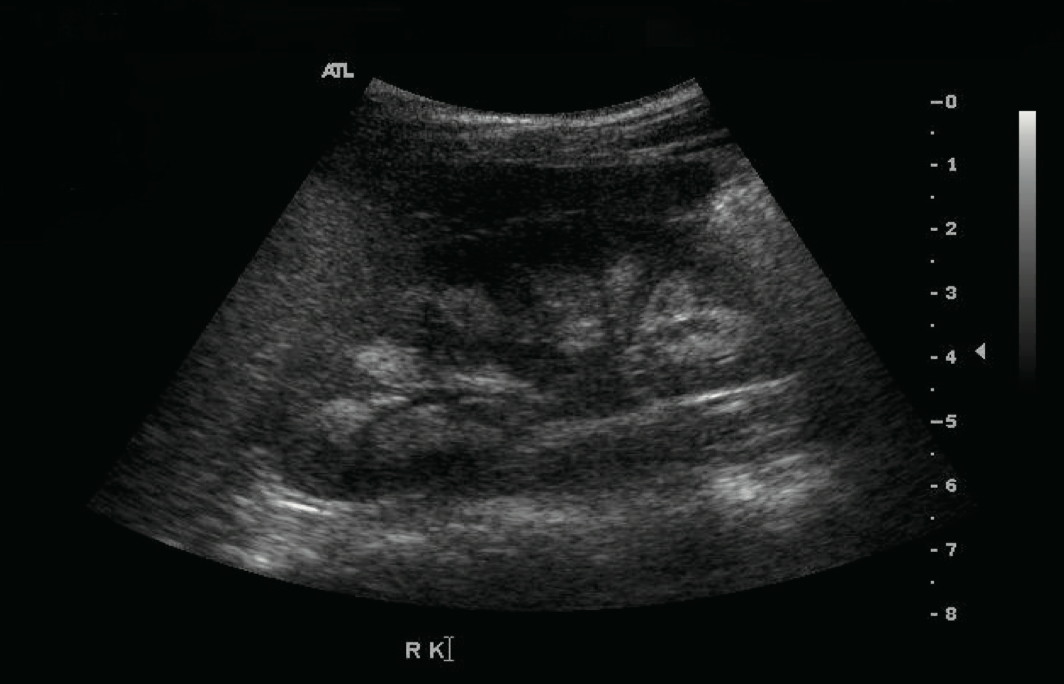

This patient was followed because of hypocalcemia, hypokalemia, and hypomagnesemia. The disorder was detected soon after birth. She had generalized seizures on the 14th day after birth. Her initial laboratory results showed hypocalcemia, hypomagnesemia, and a low level of PTH. Oral calcium, magnesium, and vitamin D supplements were prescribed and the seizures were controlled. However, if she stopped her medication, she had a seizure. Thiazide was added because of hypercalciuria and medullary nephrocalcinosis (Figure)